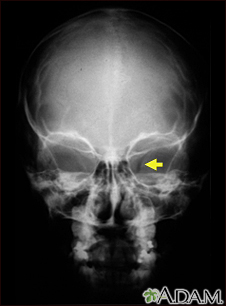

Neurofibromatosis I - enlarged optic foramen